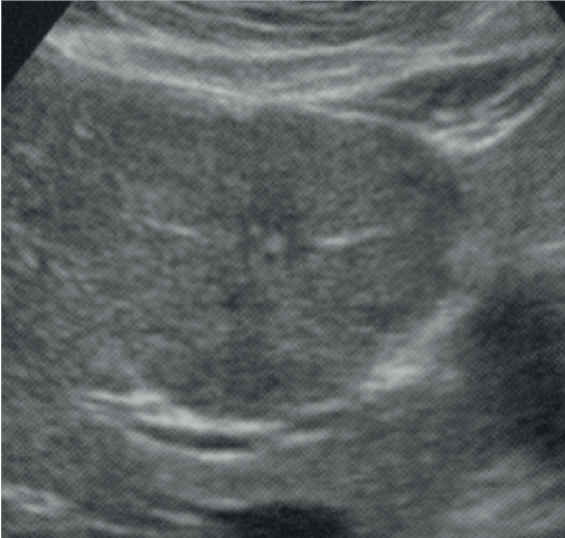

Considerando a imagem acima e as características de hiperplasia nodular focal, é incorreto afirmar que